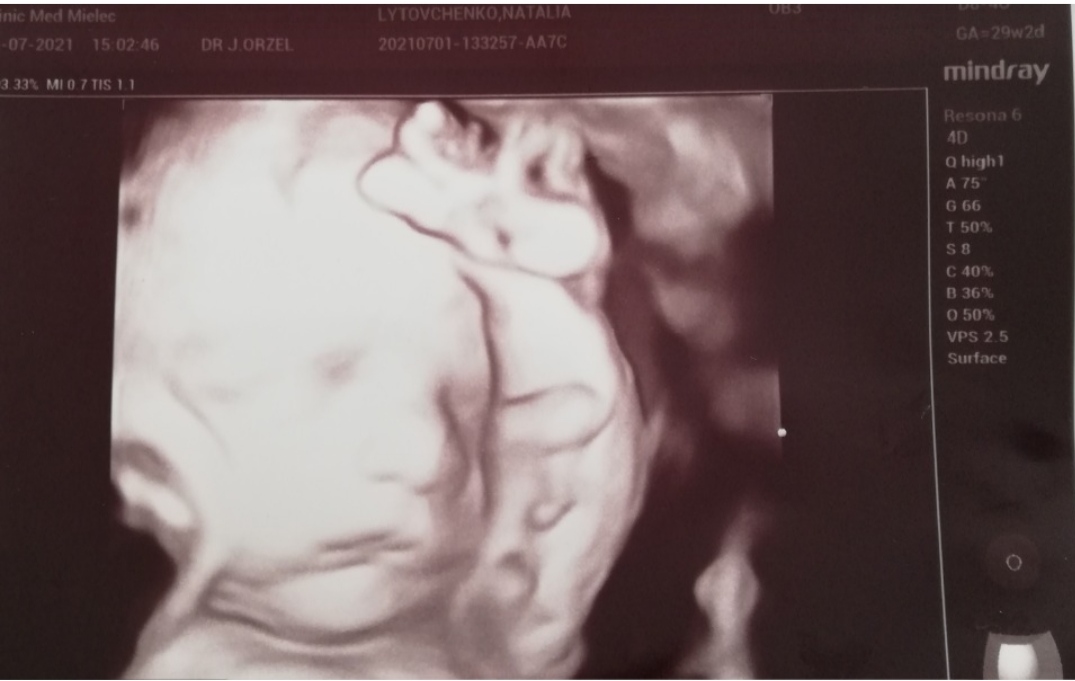

Musiała opuścić wynajęte mieszkanie, bo nie była w stanie się utrzymać i je opłacać. Warunkowo mieszka u starszego pana w zamian za pomoc przy domu. Dowiedziała się, że pod sercem nosi synka, jednak dostała też tragiczną wiadomość, że u dziecka stwierdzono wadę serca.